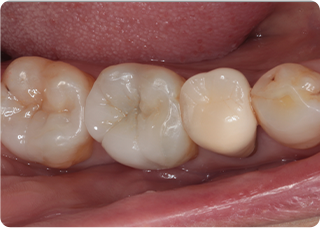

セラミックオーバーレイ症例①

術前

術中

術後

| 主訴 | むし歯の歯を治療をしたい |

| 治療期間/回数 | 3週間、3回 |

| 価格(税込) | 77,000円(税込) |

| リスク・副作用 | セラミックの破損、一時的な知覚過敏が生じる場合がある |

| ポイント | ラバーダム防湿下で接着することにより、歯とセラミックが一体化することを狙った。オーバーレイにすることで、歯ぐきに近い健康な歯質を削らずに治療することができる。 |